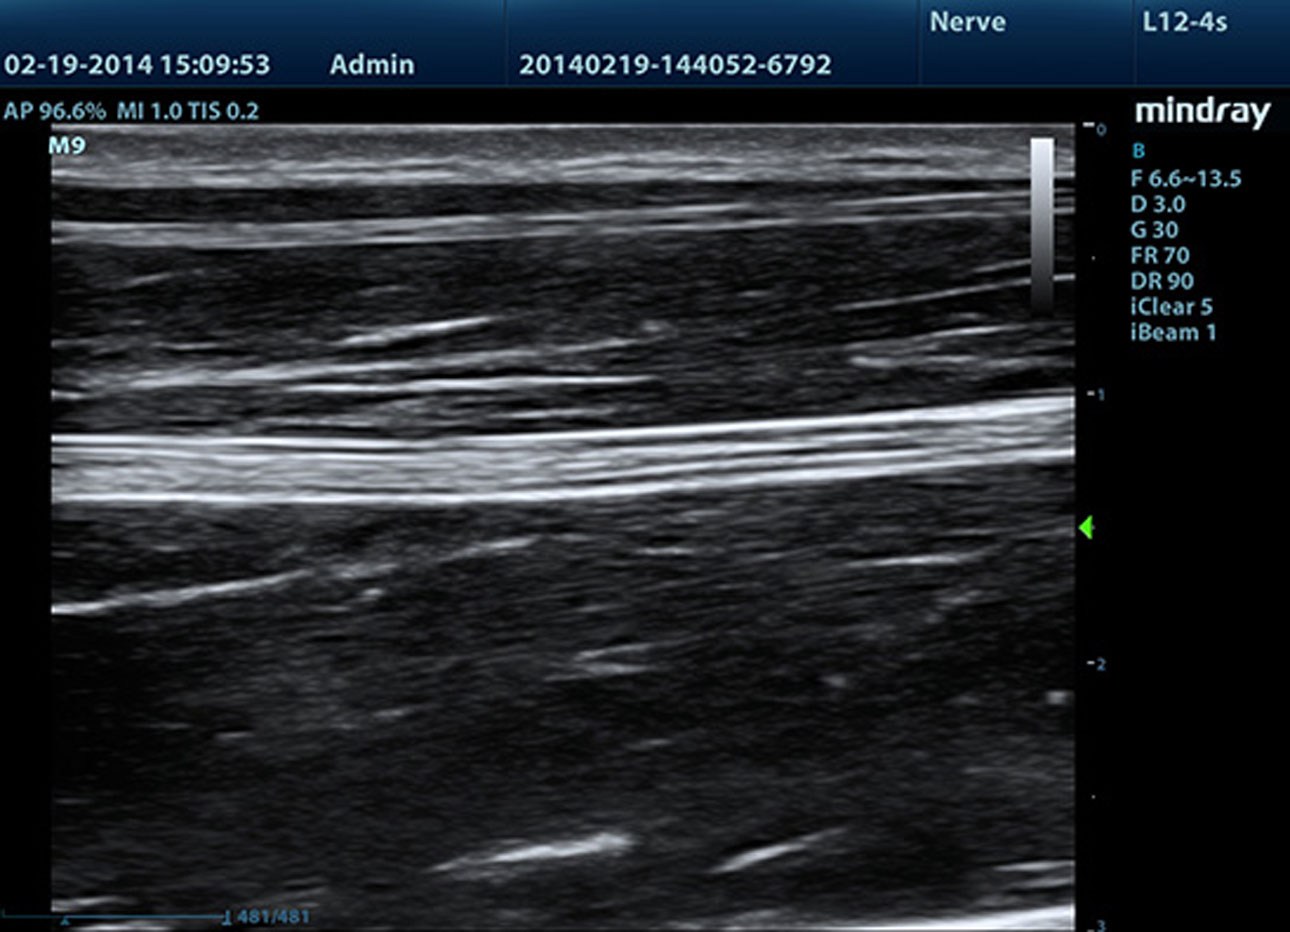

iNeedle? (Needle Enhancement Visualisation)

Advanced needle visualisation can be achieved even during steep-angled procedures. Superior image quality enhances location accuracy to minimise harm to surrounding tissue.